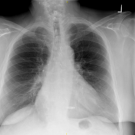

Michael Grover, DO; Sethu Sandeep Koneru, MBBS

A 74-year-old man presented to the clinic complaining of chest pain. He described the pain as an intermittent discomfort, which was localized to the middle of the sternum without radiation.